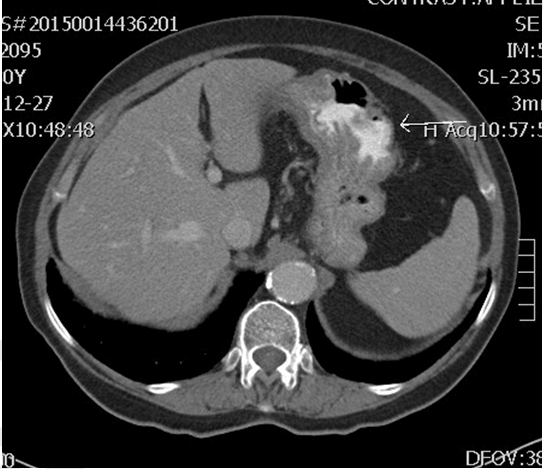

Upon initial investigation by the patient's general practitioner, a barium swallow revealed a 5x4 cm gastric lesion with irregular contour located at the junction between the proximal third and the middle of the stomach. An upper gastrointestinal endoscopy was further performed and revealed two distinct, raised, ulcerated lesions in the stomach. A contrast-enhanced thoracic-abdominal-pelvic computed tomography (CT) scan was performed to rule out metastases. The CT scan revealed no signs of metastases (Figure 1).

Figure 1: Contrast-enhanced axial computed tomography of the abdomen revealing a cavitary lesion in the stomach filled with contrast (arrow).